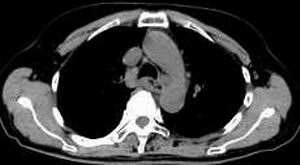

女,61岁,吞咽困难(包括开水)已久。

食道中上段癌并锁骨上窝淋巴结转移.

1、同意食道上段ca併淋巴结转移。

2、做食道呑钡就一目了然。

3、右侧甲状腺是否有问题?是否甲状腺ca转移食道上段。因为肿块顶部图像没有,请楼主展示,谢谢!

食道中上段中分化鳞癌伴锁骨上淋巴结转移

大家都很正确,谢谢!